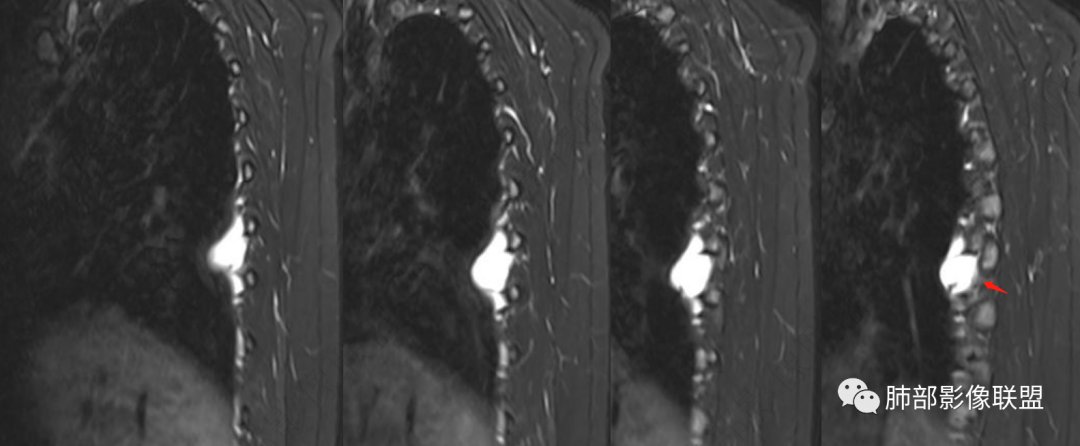

MRI表现:病灶多呈长T1长T2信号影,T2WI脂肪抑制序列呈高信号具有特征性,有时可显示流空血管影,弥散多不受限,增强后强化方式多样,与CT强化类似。

中青年女性,胸痛就诊,CT检查发现右后纵隔占位,病灶位于后胸壁纵隔移行区,略呈卵圆形或梭形蔓延,质地软,等/稍长T1、显著长T2信号,T2W脂肪抑制序列“亮灯”样高信号,这种磁共振信号特征对血管瘤具有强烈提示意义!(实在是太亮了,严格意义上的肿瘤罕见)

病灶显著强化,强化与纵隔大血管相仿且同期,一般会提示是血管源性病变,如血管瘤,如果边缘结节样强化逐渐填充渐进,则提示可能为海绵状血管瘤。